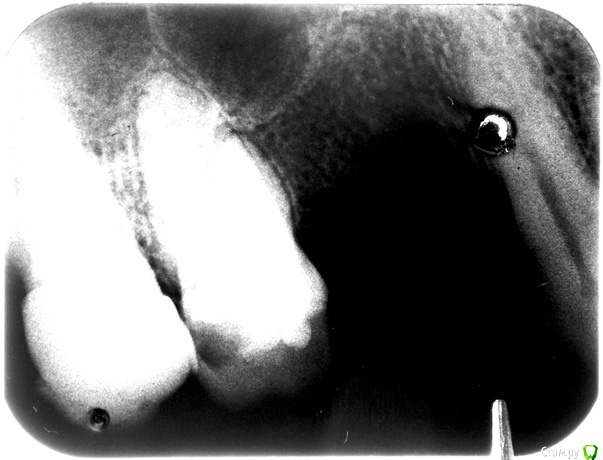

Анбо Опубликовано 15 февраля, 2017 Автор Поделиться Опубликовано 15 февраля, 2017 (изменено) ОПТГ нет. Сходил к другому врачу. Сказала, что снимок плохой (темный), но тоже увидела кариес корня и кисту. Вряд ли они сговорились. Но они зато видели снимок «живьем». Может плохой снимок + потеря качества при перефотографировании привели к тому, что на приведенном здесь фото что-то теряется? Вот поиграл светом-тенью – может что-то проявилось? Это не то, что стрелочками обозначил? Но она была не столь категорична по поводу удаления («Лучше удалить, но можно пока оставить. Но все равно через некоторое время все вернется»). И сказала, что если зуб вскрывать, то будет еще хуже. Мне сделали разрез, чтобы выпустить гной, и назначили азитромицин. Прокомментируйте, пожалуйста.Если на снимке не все видно, укажите, пожалуйста, какие части наиболее важны, я могу в фотошопе сделать их наиболее контрастными. Гистологическое исследование, о котором писал red_butler, не везде делают? Оно имеет какое-нибудь более конкретное название? Изменено 15 февраля, 2017 пользователем Анбо Ссылка на комментарий

Гарриевич Опубликовано 15 февраля, 2017 Поделиться Опубликовано 15 февраля, 2017 это дно верхнечелюстной пазухи"кисты" не видать 5 Ссылка на комментарий

DmitrySH Опубликовано 16 февраля, 2017 Поделиться Опубликовано 16 февраля, 2017 Если у Вас еще сохранились сомнения, то сделайте КТ , все будет понятно. Никакой кисты, просто бухта гайморовой пазухи. 1 Ссылка на комментарий

Bier Опубликовано 16 февраля, 2017 Поделиться Опубликовано 16 февраля, 2017 там четко есть гранулема на медиальном корне. Может ее и назвали "кистой"?? 2 Ссылка на комментарий